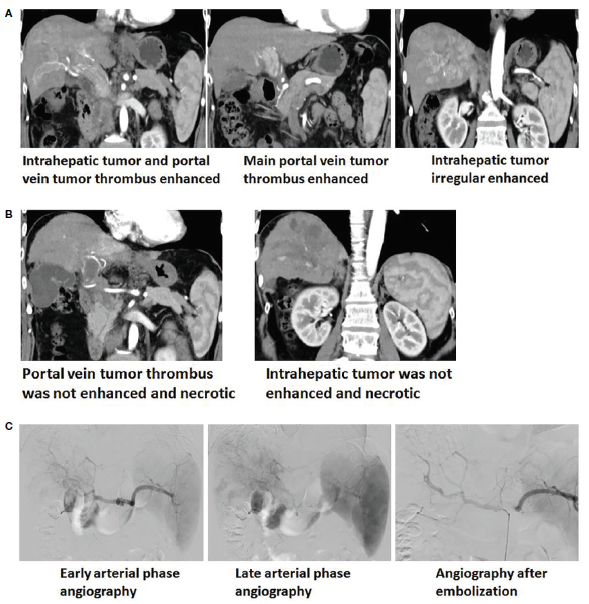

肝癌患者mTACE术前术后增强CT及血管造影图像

研究团队使用流式细胞术,分别检测健康对照组、肝硬化组和33例应用mTACE治疗的中晚期肝癌患者组,在术前1天、术后1~2周和3~5周外周血中Treg细胞和CD4+/CD8+T细胞比例变化。研究结果显示,肝癌患者外周血Tregs细胞比例明显高于健康对照组和肝硬化组,并与肝癌患者的肿瘤分期、AFP和PIVKA-II水平、肿瘤大小、是否存在肿瘤包膜及肿瘤血管侵袭等密切有关,如肿瘤分期更晚的BCLC C期肝癌患者,患者外周血中Treg细胞比例高于B期肝癌患者。但经过mTACE治疗,术后1~2周和3~5周,Treg细胞频数分别为8.54%± 1.27%和7.59%± 1.27%,均显著低于术前水平(11.74 ± 1.67%)。外周血中CD4+/CD8+T比值与肝癌患者的免疫功能呈正相关,研究团队发现mTACE术后该比值较术前也显著升高,上述研究结果表明mTACE术后,随着肿瘤显著坏死,患者自身的抗肿瘤免疫功能显著增强。